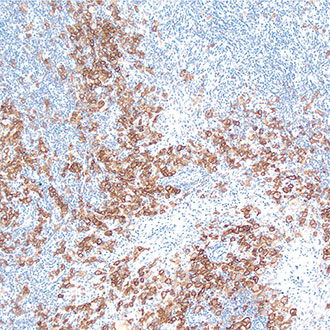

CD8

CD8 -